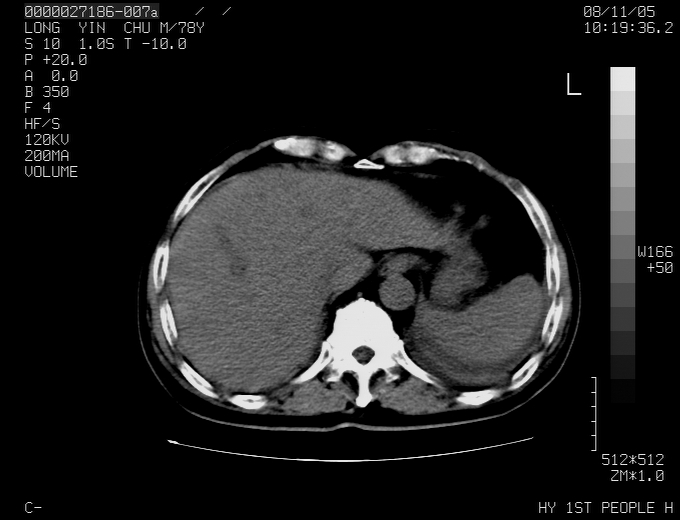

标题: CT16532:M78Y,肝脏病变,请会诊 [打印本页]

标题: CT16532:M78Y,肝脏病变,请会诊

腹胀,腹痛就诊,男性,78岁,外院b超未见异常。

肝ca,脾肾转移

考虑弥漫性肝癌并脾及双肾转移.双侧胸水.

图片质量欠佳:多考虑:左侧肾癌。脾脏转移!胸膜转移!

肝脾肾转移瘤可能性大,左肾不除外梗塞,双侧胸水

考虑弥漫性肝癌并脾及双肾转移,双侧胸水。